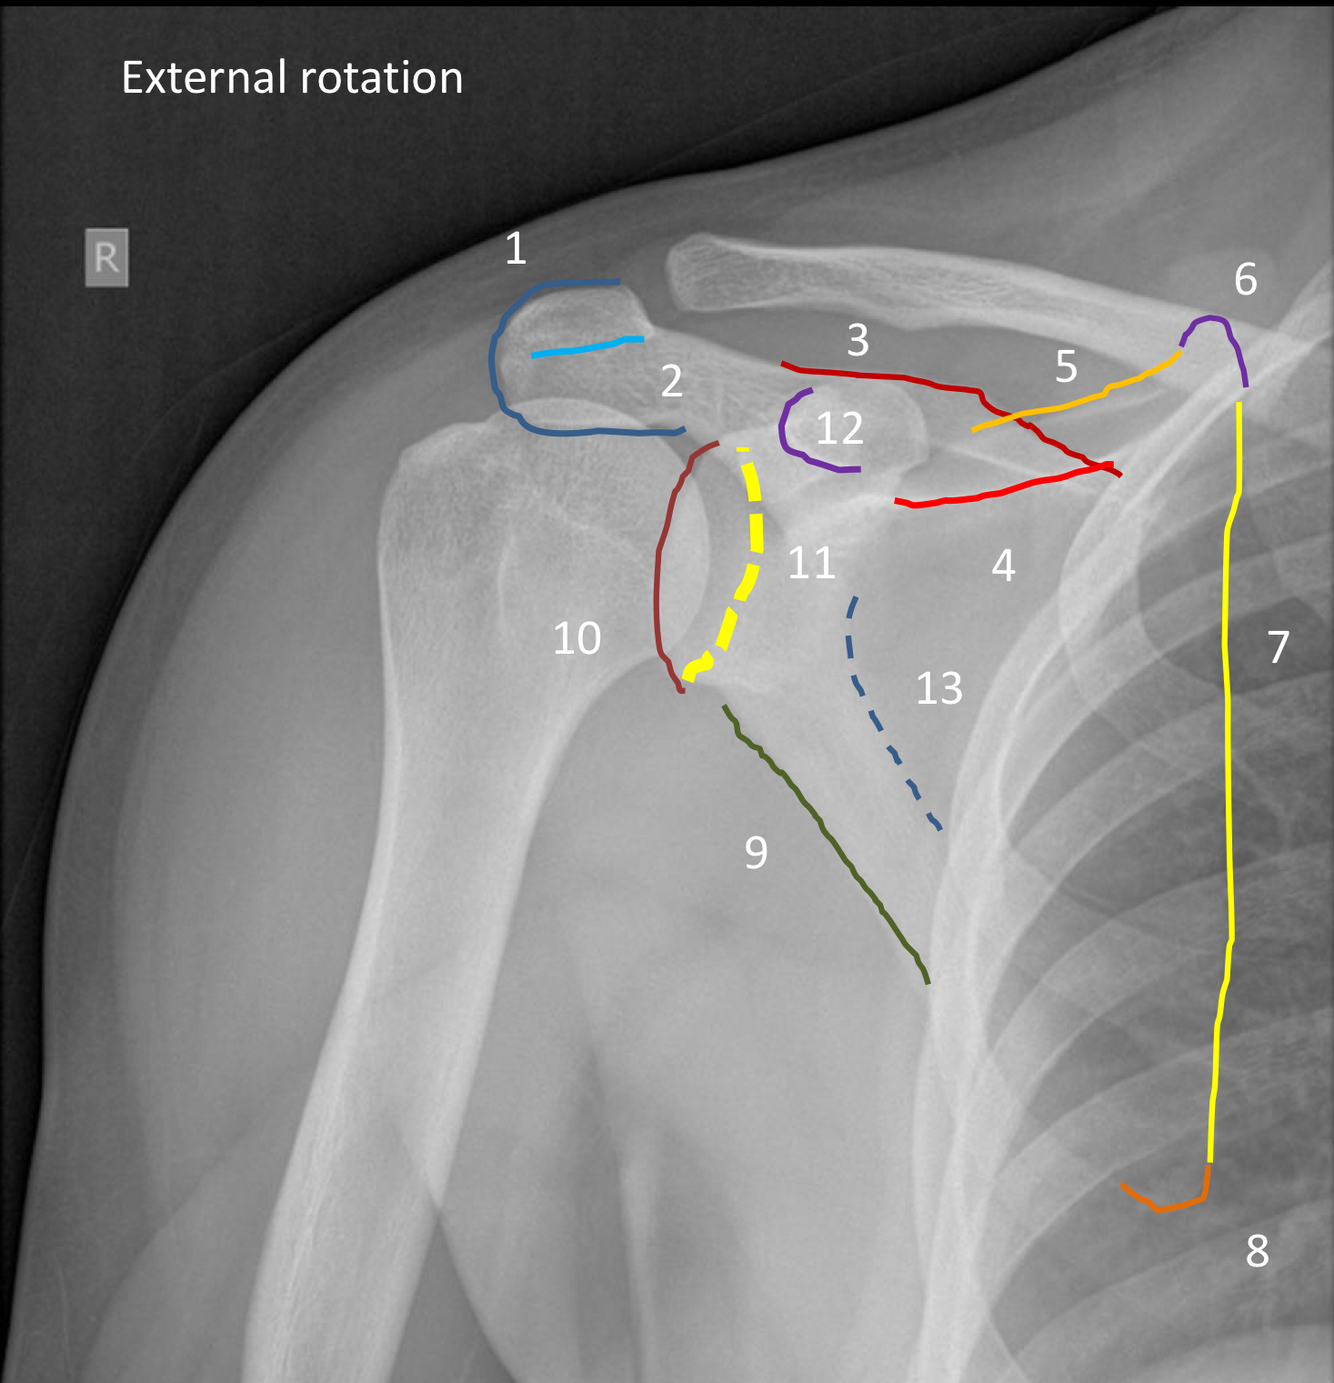

What view is this?

AP shoulder with external rotation

1?

superior margin of trapezius muscle

2?

lateral margin of deltoid muscle

3?

greater tuberosity of the humerus

4?

lesser tuberosity of the humerus

5?

humeral head

6?

medial margin of humeral metaphysis

7 (dotted purple line)?

anatomical neck of humerus

8 (green dotted line)?

surgical neck humerus

9?

deltoid tuberosity

10?

acromioclavicular joint space

11 (dark green line)?

conoid tubercle

12?

trapezoid line or ridge of clavicle